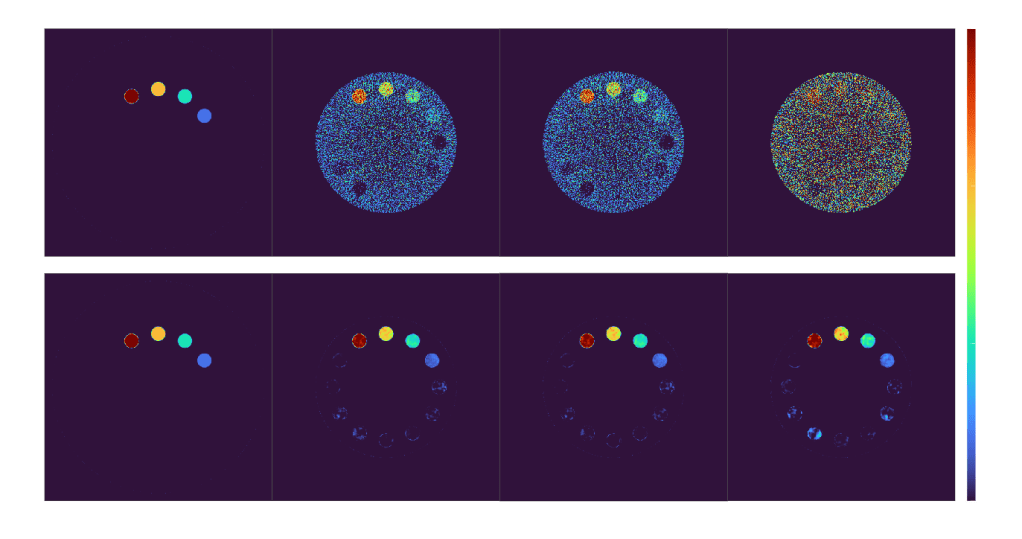

Problem – Higher Cross-Scanner Variability

Reconstructed 35 – 85 keV Mono-Energetic Images

Iodine Maps Generated Using Mono-Energetic Images

By integrating realistic, physics-informed in silico simulations with a conditional U-Net architecture, the model learns spectral-spatial relationships that allow accurate and continuous mono-energetic image synthesis across energy levels. DL-synthesized mono-energetic images show strong quantitative agreement and structural fidelity with ground-truth data, maintaining inter- and intra-scanner consistencies.

This study establishes the feasibility of using AI-based approaches, acquainted with in silico imaging frameworks that provide ground-truth mapped datasets otherwise impractical experimentally, for cross- scanner spectral harmonization – enabling standardized, scanner-agnostic imaging to facilitate quantitative CT.